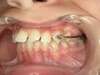

Avant